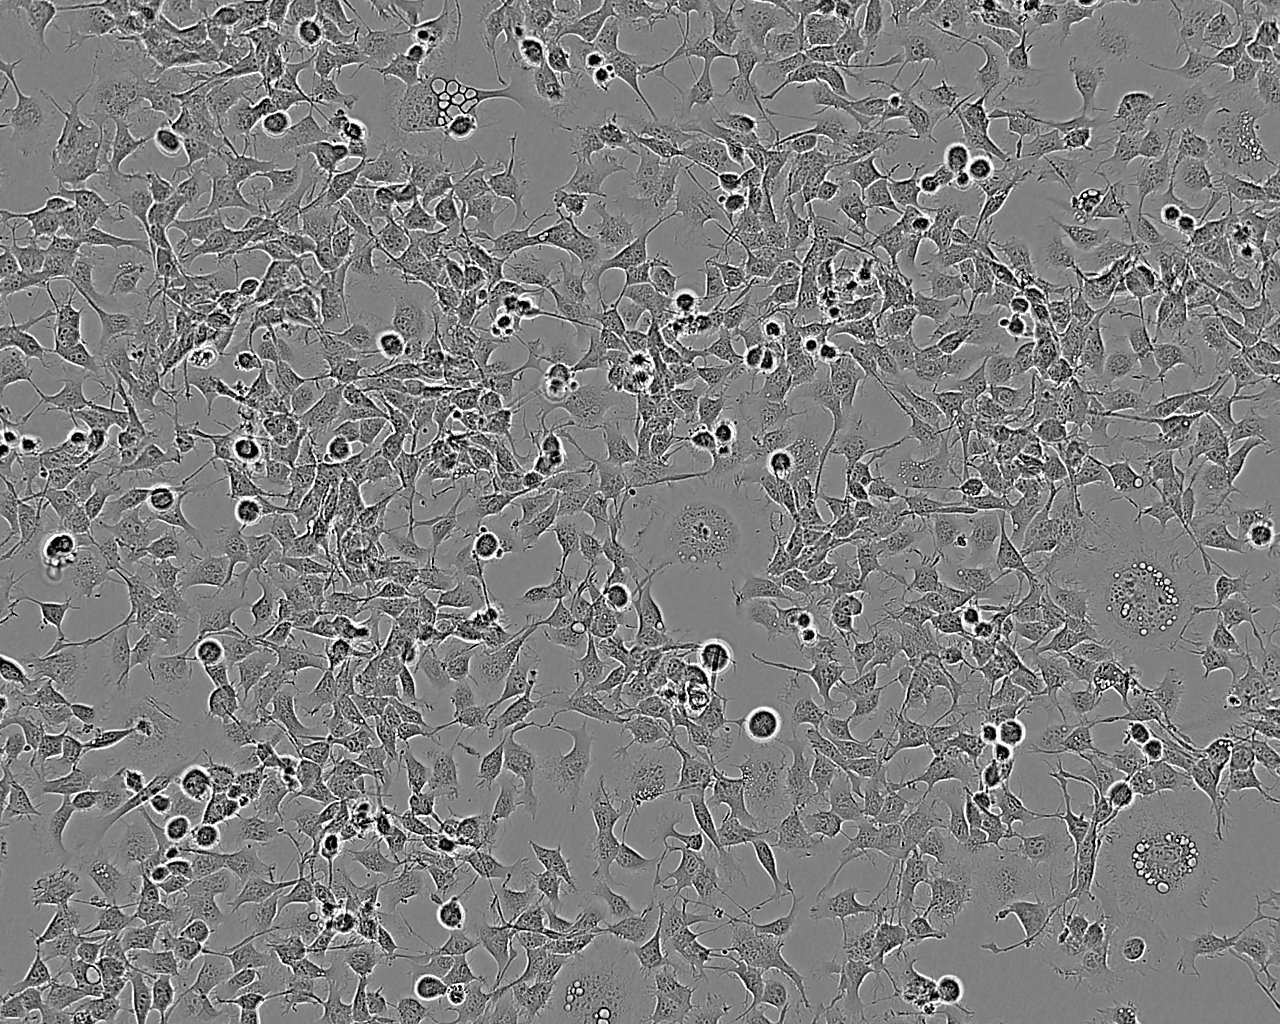

K1 人甲状腺癌细胞系

细胞形态:上皮细胞样

细胞生长:贴壁

细胞生长特性:贴壁生长